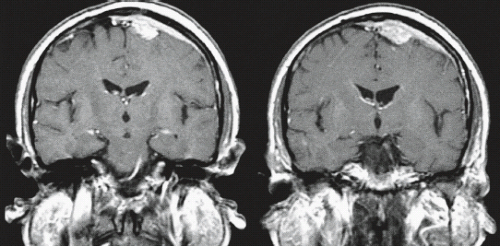

Adult Brain Tumors | Radiology Key

Adult Brain Tumors | Radiology Key from i0.wp.com

A brain tumor is a mass of abnormally growing cells in the brain or skull. Any growth inside such a restricted space can cause problems. Brain tumors are masses of abnormal cells within the brain.